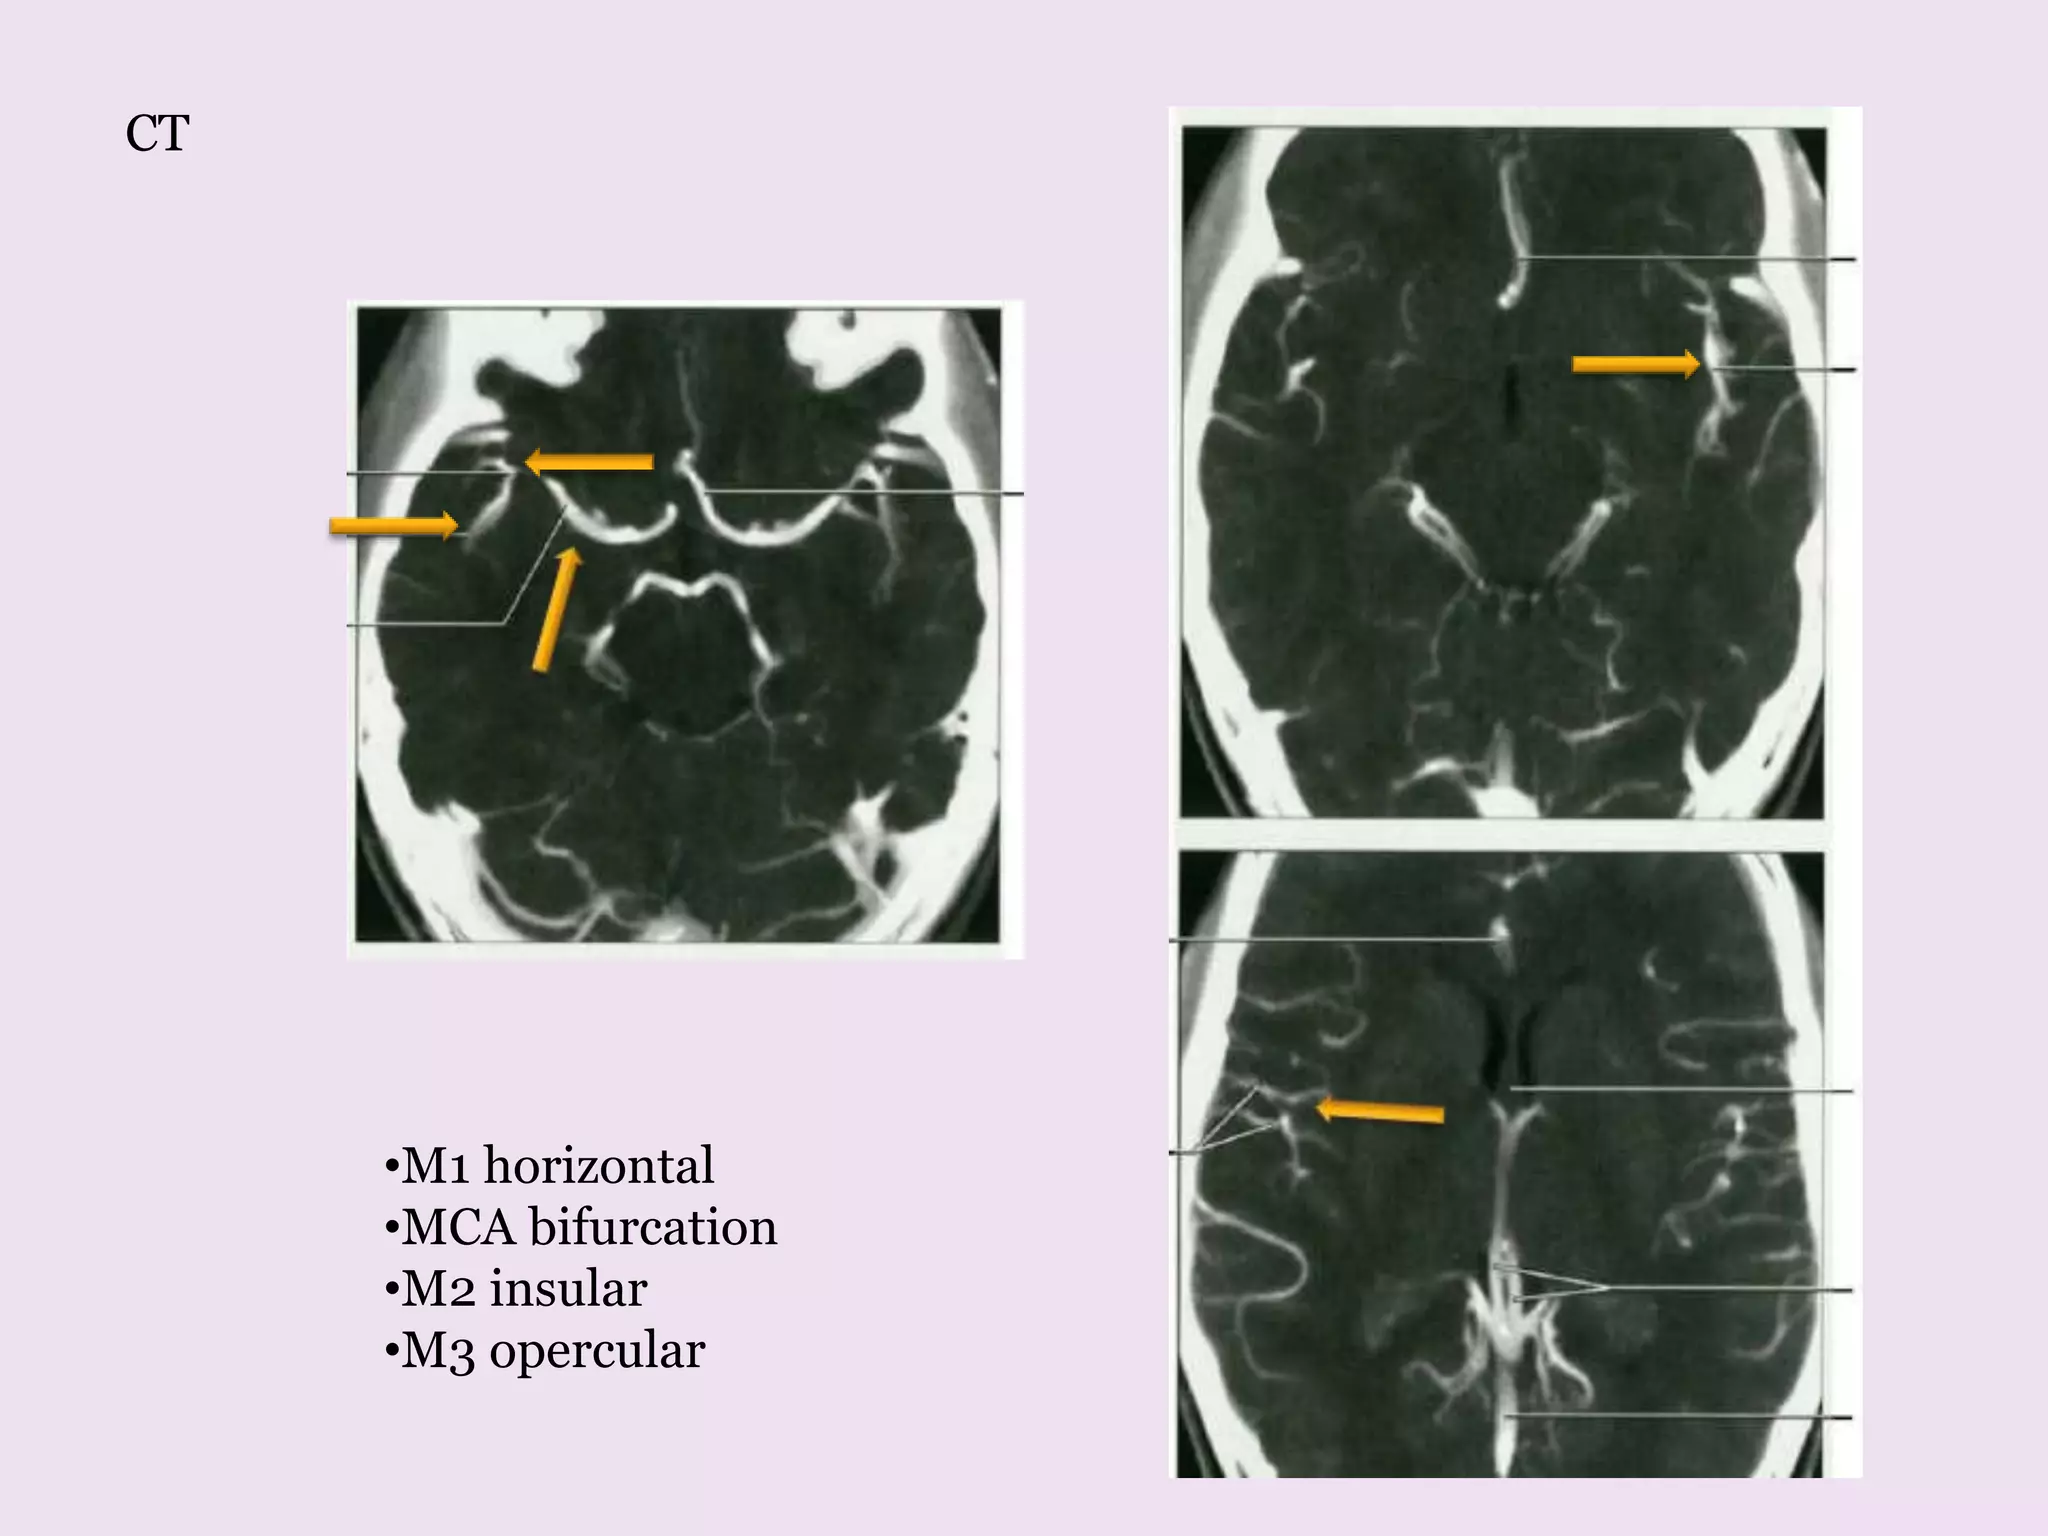

M1 horizontal

Origin -Laterally from ICA

bifurcation

Till its bi/trifurcation at

sylvian fissure.

Br – Lateral

Lenticulostriate branch

course superiorly

Anterior temporal artery

Supplies-Lentiform nucleus

Part of IC , caudate nucleus

M2 insular

At its genu divides

into branches

Loop over insula

pass laterally to exit

from sylvian fissure

M3 opercular

Emerge from

sylvian fissure

Ramify over

hemispheric surface

Supplies –cerebral

cortex and white

matter

•M1 horizontal

•MCA bifurcation

•M2 insular

•M3 opercular

CT